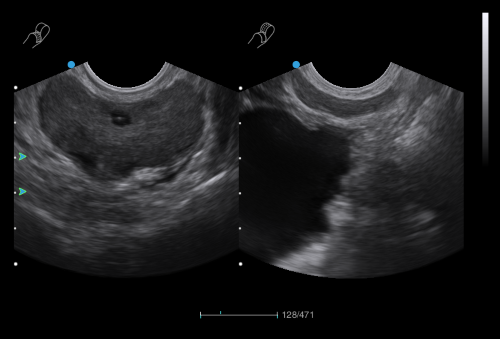

Superb Versatility in Women’s and Children’s Healthcare

The IBUS series comprises IBUS 60 and IBUS 30. IBUS is the intelligent breast volume diagnostic system that provides integrated solutions for both women and children. The specialized breast probe, standardized scanning process, and standardized diagnosis procedure guided by BI-RADS significantly enhance diagnostic accuracy for breast examinations. The cutting-edge application solutions in OB / GYN / pediatrics aim at elevating the quality of healthcare for women and children.

- More accurate and convenient for diagnosing solid-cystic tumors

- Higher detection rate of tumors in dense breast

- Display breast with volume ultrasonic tomography

- Easily acquire images of coronal, transverse, and sagittal planes